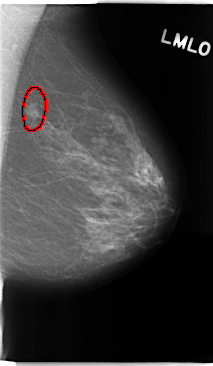

C_0135_1.LEFT_MLO

LEFT_MLO LINES 4752 PIXELS_PER_LINE 2760 BITS_PER_PIXEL 12 RESOLUTION 50 OVERLAY

FILE: C_0135_1.LEFT_MLO.OVERLAY

TOTAL_ABNORMALITIES 1

ABNORMALITY 1

LESION_TYPE MASS SHAPE IRREGULAR MARGINS MICROLOBULATED

ASSESSMENT 4

SUBTLETY 5

PATHOLOGY MALIGNANT

TOTAL_OUTLINES 1

BOUNDARY